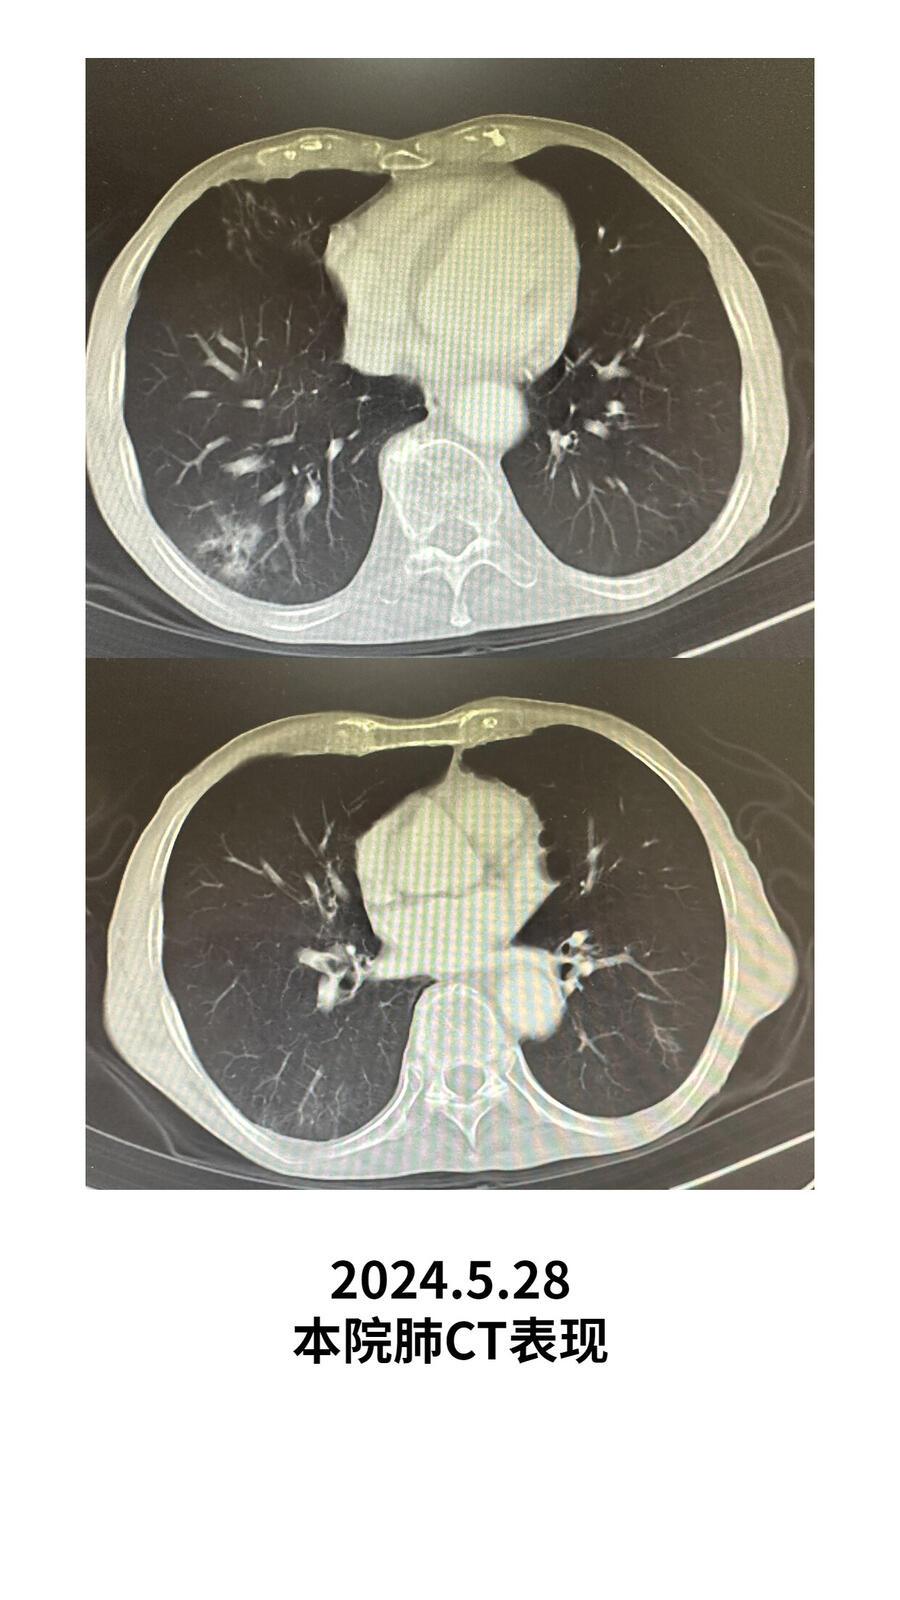

抗炎两周后复查肺CT,右肺占位明显缩小变淡,考虑炎症。